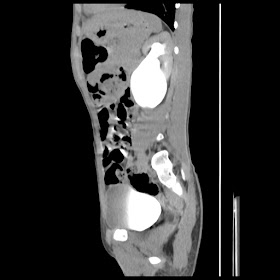

current CT images: